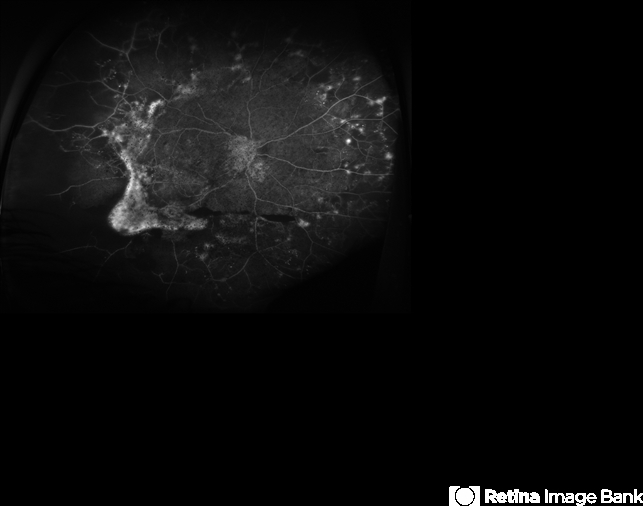

- ultra-wide field imaging, fluorescein angiogram (FA), FA early phase, hyperfluorescence, neovascularization (NV), fibrotic neovascularization, asteroid hyalosis

- Ultra-widefield fluorescein angiogram of a 47-year-old male with severe prolifterative diabetic retinopathy with very extensive neovascularization with fibrosis and traction affecting his right eye. The patient also has asteroid hyalosis affecting the eye. He was diagnosed with Type 1 diabetes in the late 1970s. The patient's vision sc20/100 PH20/70-2. He received treatment of panretinal photocoagulation following the angiogram.